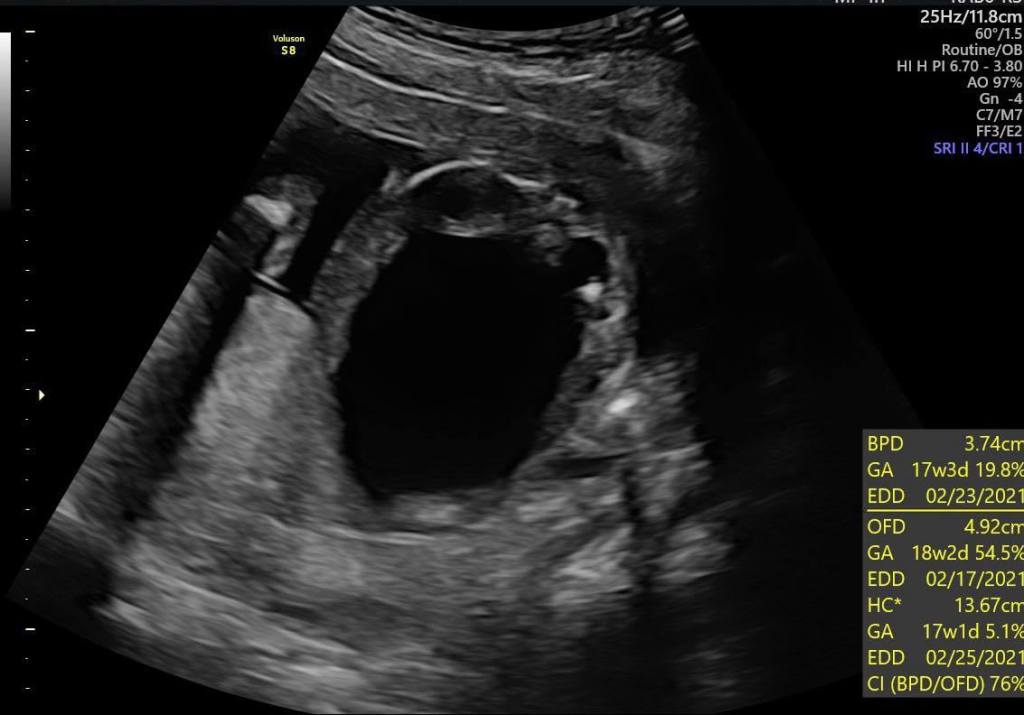

胎兒巨膀胱

我們要穿過媽媽的肚皮還有子宮還有羊水腔

然後把這根管子放到寶寶的膀胱跟羊水腔中間硬殺出一條通路